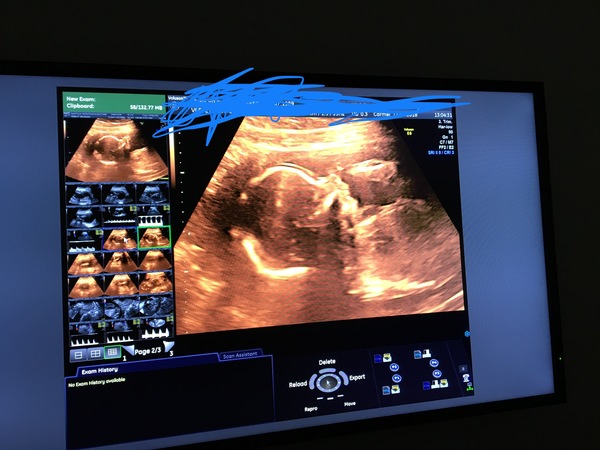

We had our 20 week scan yesterday.

We’re having a boy. I’d have preferred a girl, no real definable reason, think it’s just what I’m most familiar (and therefore comfortable) with. Pretty sure by the time he arrives I’ll have convinced myself that a boy is best!

But the scan also picked up a moderately echogenic bowel. There was evidence of blood in my amniotic fluid, so the most likely explanation is that he swallowed some blood and that’s caused the echogenic bowel. I can’t help worrying though. The sonographer said she was referring it on for a second opinion and we’d be contacted in about 2 weeks. That feels like a very long time to wait. :(